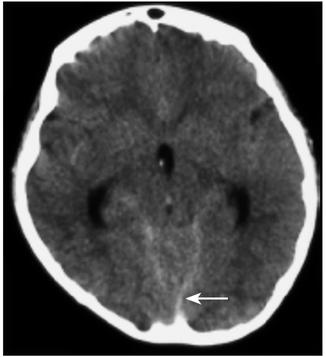

诊疗经过:入院后行腰椎穿刺术,连续留取3管脑脊液,均为淡红色血性脑脊液,脑脊液化验结果除外中枢神经系统感染。2010年10月28日晚19时40分患儿站立中诉腿疼,平卧后再次出现抽搐,表现为口吐白沫、双手握拳、双上肢屈曲、颈部强直,并有意识障碍。予吸氧、镇静止惊、改善脑水肿等对症治疗,仍反复抽搐多次。急诊行颅脑CT检查,示脑室及蛛网膜下腔少量出血(图3)。遂由儿内科转神经外科治疗。转科后行全脑全脊髓血管造影提示:T11~L2脊髓血管畸形(图4)。遂于2010年11月10日在全麻下行T11~L2脊髓畸形血管团切除+椎板扩大成形+硬膜修补术。术后给予脱水、抗炎、止血、补液、支持、神经营养、激素等治疗后患者意识逐渐转清,未再抽搐,病情稳定出院。

图3 第三次颅脑CT检查(2010年10月28日):脑室及蛛网膜下腔少量出血(箭头)

本例患儿以反复抽搐为首发症状,脊髓症状不明显,虽在外院曾行颅脑CT检查,但因为出血量较少考虑为血管影未予重视,头CT报告未提示有颅内出血。住院后行腰穿脑脊液呈淡淡的红色,术者考虑是损伤。入院后的颅脑CT报告正常。患儿入院第5天活动后很快出现抽搐、意识障碍,再次复查CT,显示脑室及蛛网膜下腔少量出血。急转神经外科后行全脑全脊髓血管造影提示:T11~L2脊髓血管畸形。